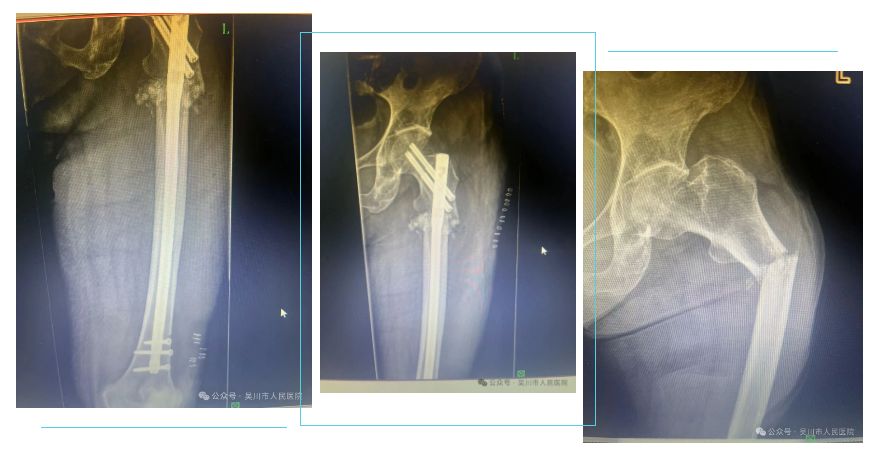

病例二:该患者为青年男性,外伤致股骨干闭合性骨折,给予股骨干骨折闭合复位髓内钉内固定术,术后可早期下地锻炼。髓内钉技术属于微创操作——采用闭合穿钉技术,软组织剥离少,保留了骨折血肿,减少了对骨膜血运的破坏,可以不暴露骨折部位而复位骨折端,降低了骨折不愈合的风险及手术感染率。